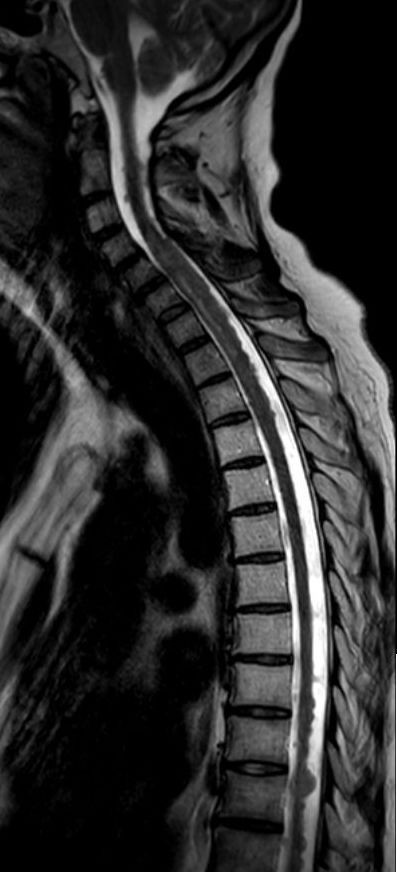

Rückenmarks-Metastasen

48-jährige Patientin mit einem kleinzelligen, neuroendokrinen Bronchialkarzinom. Taubheit der Füße, Kraftminderung und Hypästhesie beider Beine.

RM-Metastasen

Rückenmarks-Metastasen Rückenmarks-Metastasen Rückenmarks-Metastasen